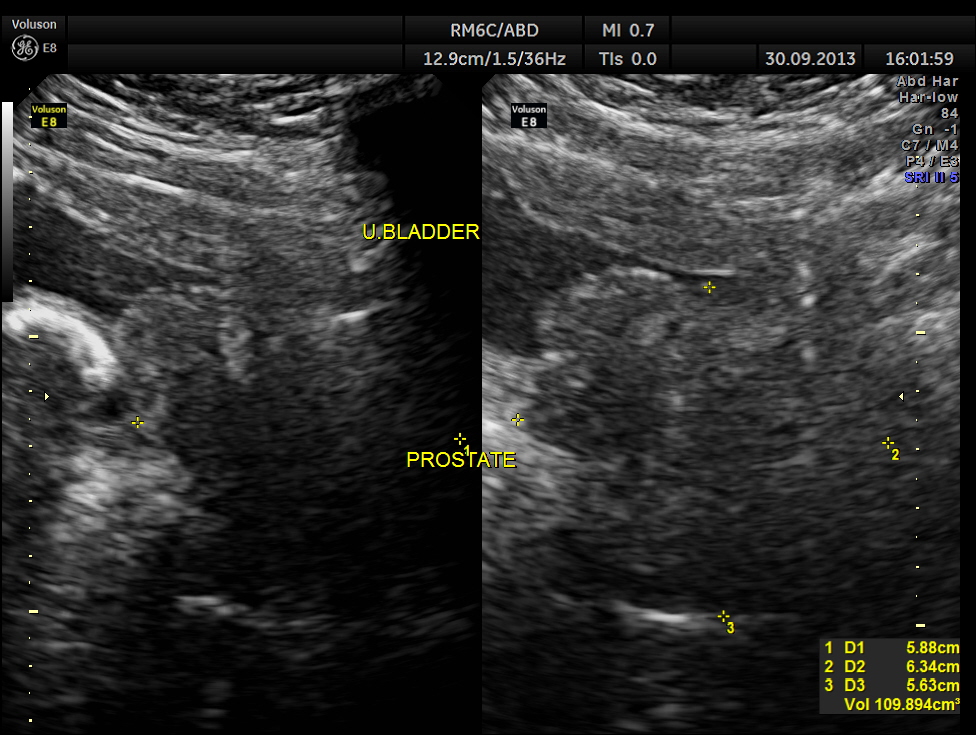

This was a 57 year old gentleman , with complaints of difficulty in passing urine and dysuria of 1 month duration.

urinary bladder showed a large calculus and prominent swelling of the median lobe of the prostate.

enlarged prostate and median lobe hypertrophy

The diagnosis given was Large calculus in the urinary bladder , Severe prostatic enlargement with prominent median lobe hypertrophy , causing Right sided obstructive uropathy.